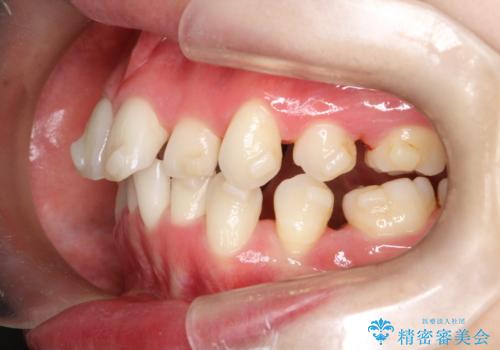

【抜歯インビザ】前歯の凸凹をなおしたい

- 前歯の凸凹を主訴に来院されました。

前歯はあまり下げる必要がなかったため、上下左右の第二小臼歯抜歯を行う治療計画としました。

途中、臼歯の近心傾斜を認めましたが、追加アライナーを使用することでリカバリーを行いながらインビザラインのみで治療を完了することができました。